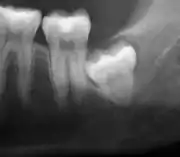

Impacted wisdom teeth are classified by their direction of impaction, their depth compared to the biting surface of adjacent teeth and the amount of the tooth's crown that extends through gum tissue or bone. Impacted wisdom teeth can also be classified by the presence or absence of symptoms and disease. Screening for the presence of wisdom teeth often begins in late adolescence when a partially developed tooth may become impacted. Screening commonly includes a clinical examination as well as x-rays such as panoramic radiographs.

Impacted wisdom teeth are classified by the direction and depth of impaction, the amount of available space for tooth eruption, and the amount of soft tissue or bone (or both) that covers them. The classification structure helps clinicians estimate the risks for impaction, infections and complications associated with wisdom teeth removal.[6] Wisdom teeth are also classified by the presence (or absence) of symptoms and disease.[7]

Impacted wisdom teeth are often described by the direction of their impaction (forward tilting, or mesioangular being the most common), the depth of impaction and the age of the patient as well as other factors such as pre-existing infection or the presence of pathology (cysts, tumors or other disease).[5]: 143–144 Each of these factors is used to predict the difficulty (and rate of complications) when removing an impacted tooth, with age being the most reliable predictor[8] rather than the orientation of the impaction.[9]

If the tooth cannot be assessed with clinical exam alone, the diagnosis is made using either a panoramic radiograph or cone-beam CT. Where unerupted wisdom teeth still have eruption potential several predictors are used to determine the chance of the teeth becoming impacted. The ratio of space between the tooth crown length and the amount of space available, the angle of the teeth compared to the other teeth are the two most commonly used predictors, with the space ratio being the most accurate. Despite the capacity for movement into early adulthood, the likelihood that the tooth will become impacted can be predicted when the ratio of space available to the length of the crown of the tooth is under 1.[5]: 141